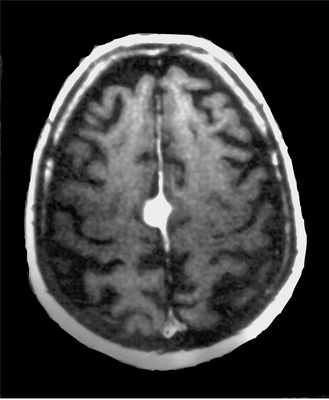

Менингиома в детском возрасте составляет всего 1-2% от случаев этой опухоли. Обычно она связана с нейрофиброматозом II типа. Внутрижелудочковые менингиомы у детей встречаются в 20%, в то время как у взрослых в 10 раз реже.

МРТ головного мозга. Нейрофиброматоз тип II. Менингиома нижнего сагиттального синуса. Аксиальная и сагиттальная Т1-зависимые МРТ с контрастированием.

Тот же пациент. Внутрижелудочковая менингиома. Аксиальная Т2-зависимая МРТ, поперечная и сагиттальная Т1-зависимые МРТ с контрастированием.